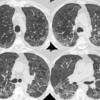

bulla LLL CT1

Date: 06/03/2004

Views: 3529

bulla LLL CT2

Views: 3566